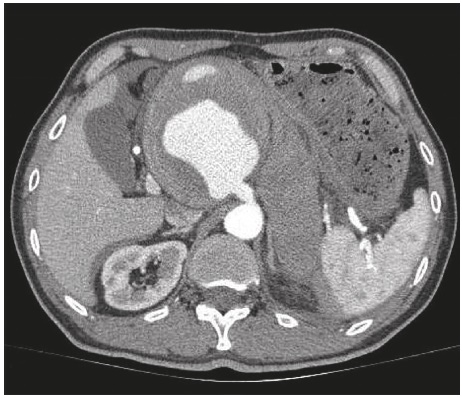

Debido a la presión arterial alta y el dolor abdominal intenso, se hizo una tomografía axial computarizada tóraco-abdominal (TAC) para el diagnóstico diferencial de abdomen agudo. La exploración mostró una disección aneurismática del tronco celíaco de 10 mm de diámetro con un trombo mural sin alteraciones aórticas (Figura 1). Ante este diagnóstico, se hizo una embolización de la lesión con implantación de un manguito aórtico endovascular a través de la arteria femoral. En la arteriografía de control se observó exclusión correcta del aneurisma sin alteraciones en la arteria mesentérica superior. La irrigación del páncreas, el bazo y el intestino dependía de la vasculatura de la arteria mesentérica superior. Un estudio eco-doppler mostró el aneurisma sin señal doppler en su interior.

Figura 1 Tomografia axial computarizada (TAC). Se observan disección aneurismática del tronco celíaco de 10 mm de diámetro con un trombo mural, y un gran hematoma a nivel del citado aneurisma así como un hematoma localizado en la parte posterior del riñón izquierdo que progresa hacia la fascia generando un hematoma periesplénico, perihepático y peripancreático